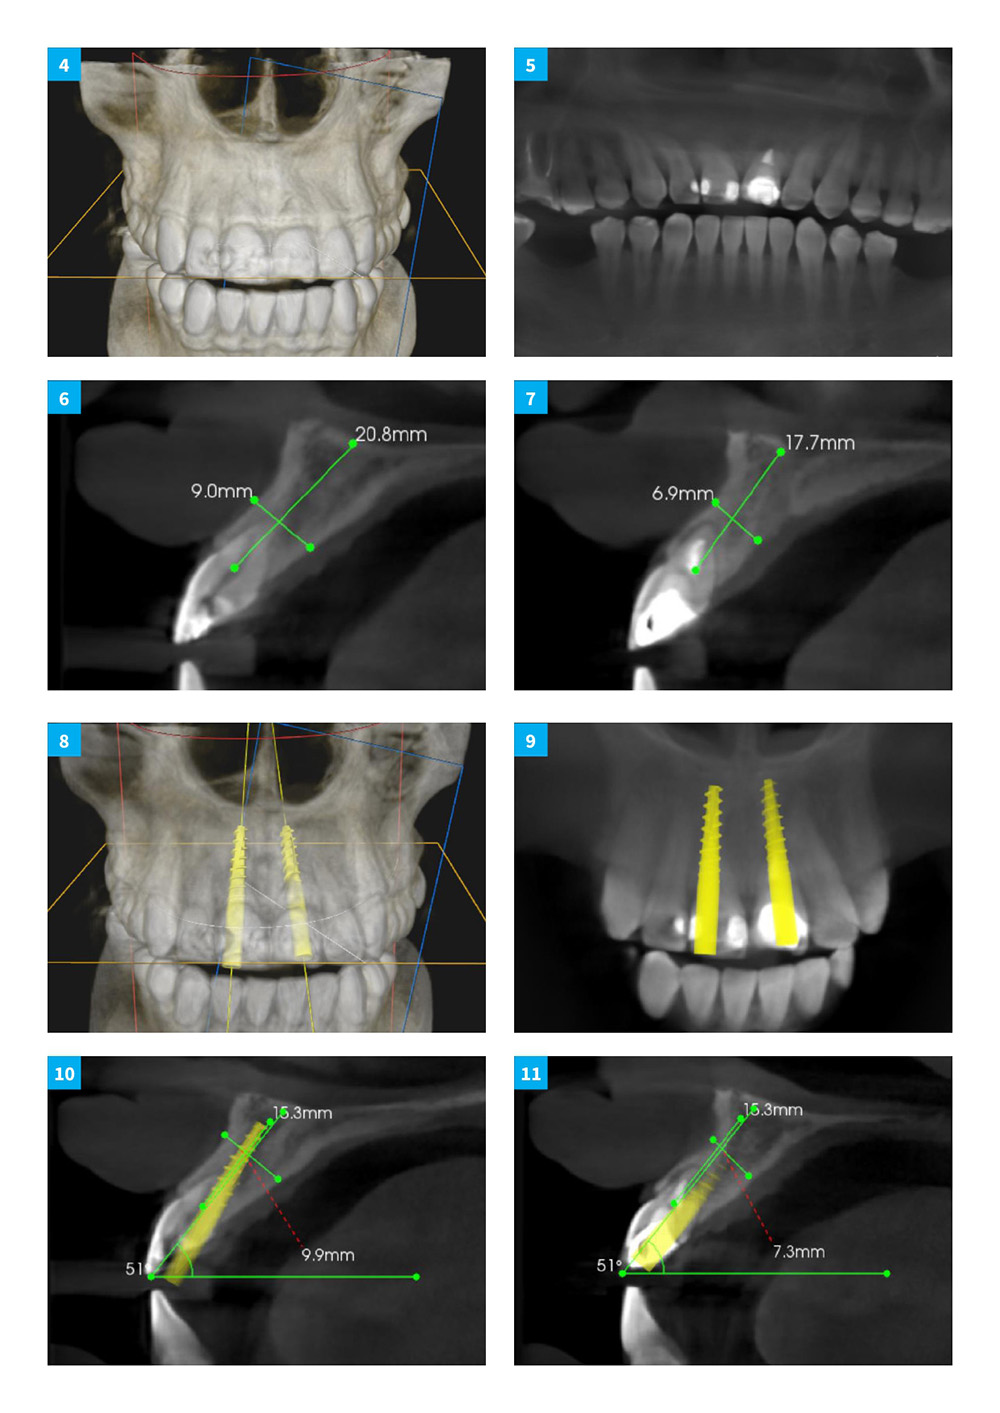

Anterior Central Teeth Extraction With Immediate Implant Loading: Multi-unit Bridge